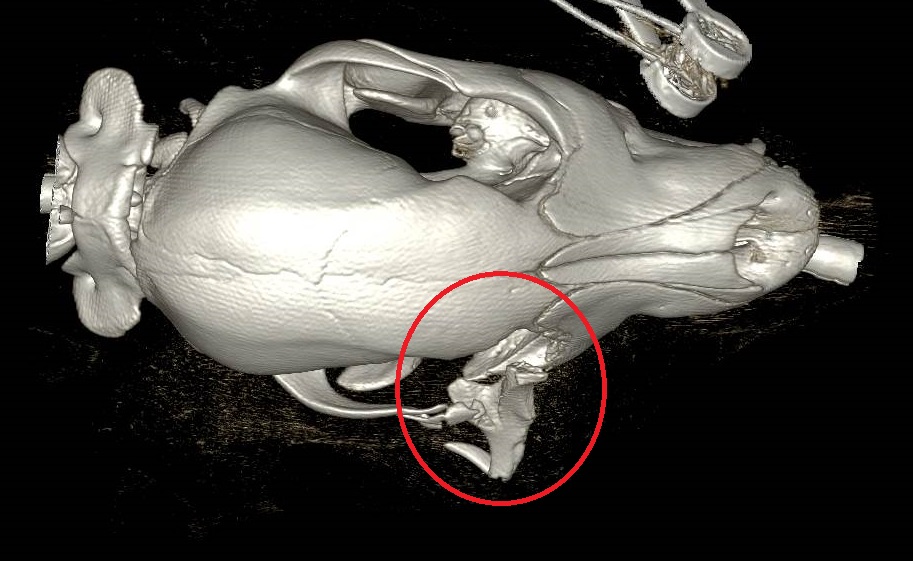

Our Specialist imaging team performed a CT scan which showed a broken bone was pressing on his Nigel’s eye (see below scan).